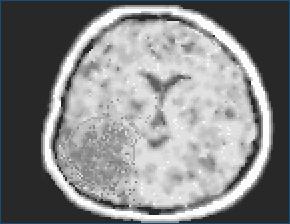

Čierna výplň lokalizovaná na okrajovej časti cerebra - to je tumor, čiže nádor.